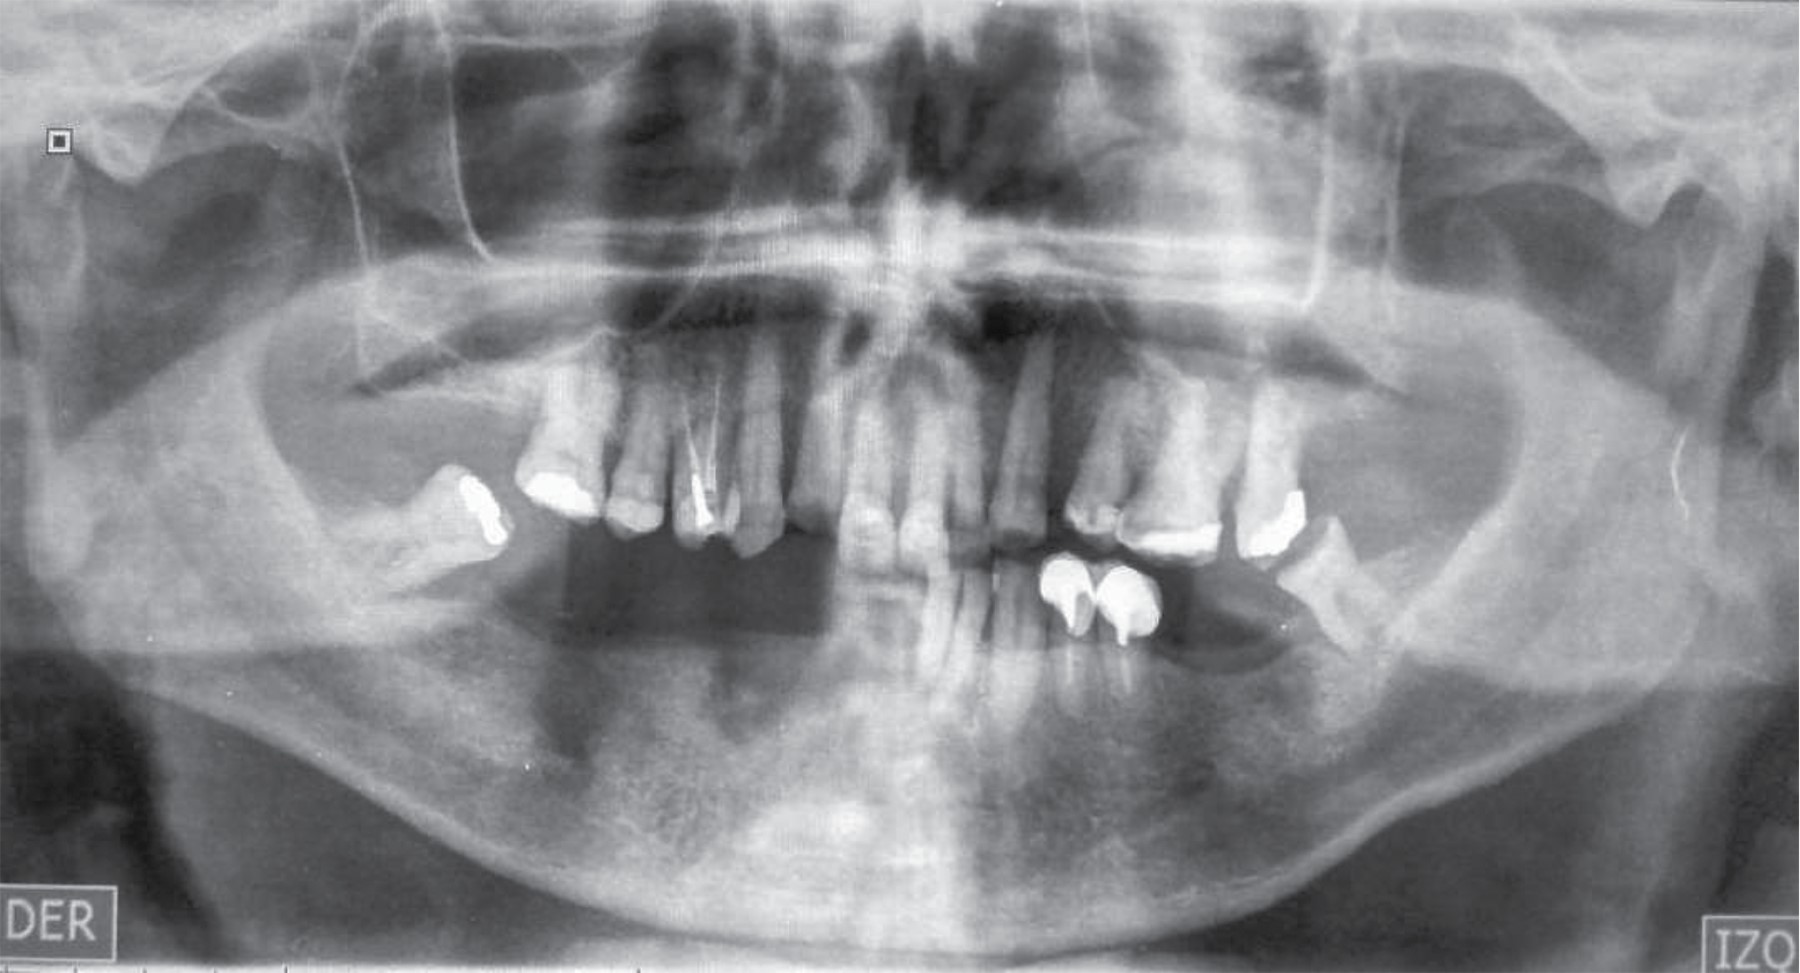

After a month and a half of presenting COVID-19 infection, he presented an increase in volume, an erythematous area, painful on palpation and the presence of abscesses in the fundus region of the left maxillary vestibule, for which he went to a dentist and drained the aforementioned abscesses. Indicates to perform orthopantomography (Figure 1) and start treatment with clindamycin and amoxicillin/clavulanic acid. He also goes to the otolaryngologist who indicates a diagnosis of sinusitis and trigeminal neuralgia for which he indicates pregabalin, B complex and carbamazepine.

Not showing improvement, he went to the Department of Oral and Maxillofacial Surgery "Dr. Atilio Perdomo"; "Dr. Ángel Larralde" Hospital, Carabobo, Venezuela. Evidence on clinical examination: partial bimaxillary edentulous patient, erythematous area in the bottom of the left maxillary vestibule, dental mobility in dental structures 25, 26 and 27 grade III, as well as mobile left maxillary alveolar ridge, also refers to paresthesias in the upper lip with accentuation of the pain and radiation to the ipsilateral eyeball. The radiographic examination revealed veiling of the left maxillary sinus with bone loss of the left maxillary vestibular table.

Figure 2